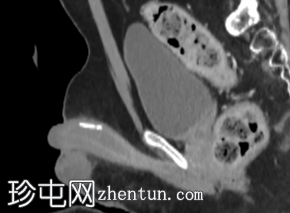

矢状位增强CT(门静脉期)

腹部和盆腔增强CT显示,沿白膜/阴茎海绵体周围走行可见钙化斑块。最大的斑块位于阴茎背侧,长度达19毫米。

本例中,因腹痛行CT检查时偶然发现阴茎背侧海绵体钙化斑块,其中最大斑块直径为19毫米,这是佩罗尼氏病钙化斑块的典型影像学表现。

CT扫描中阴茎钙化的鉴别诊断有限,可能包括既往外伤/炎症引起的营养不良性钙化、血栓形成血管钙化或罕见钙化病变;然而,斑块状的背侧海绵体分布最符合佩罗尼氏病。